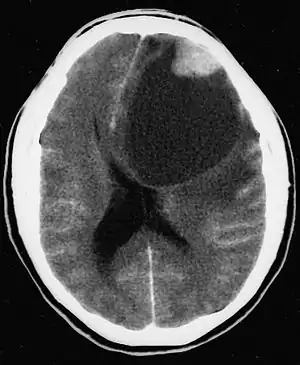

| CT scan of a brain with pleomorphic xanthoastrocytoma. The classic radiographic appearance is one of a superficially situated tumor, here a mural nodule, associated with an underlying cyst. |

Pleomorphic xanthoastrocytoma usually develops within the supratentorial region (the area of the brain located above the tentorium cerebelli). It is generally located superficially (in the uppermost sections) in the cerebral hemispheres and involves the leptomeninges. It rarely arises from the spinal cord.

- A CT scan of the brain, and/or an MRI scan of the brain and spine, will be performed. A special dye may be injected into a vein before these scans to provide contrast and make tumors easier to see.